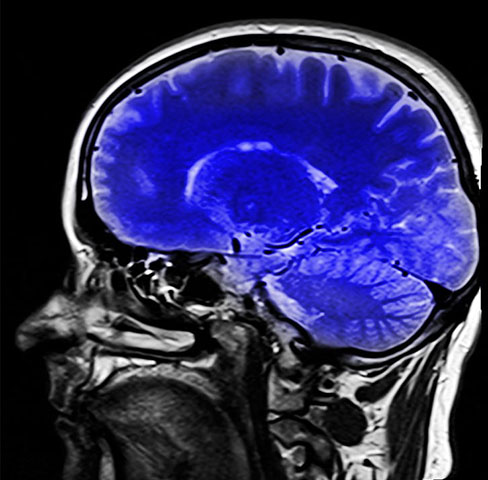

Nutriente vital para o cérebro, colina está presente em vários alimentos; veja os principais